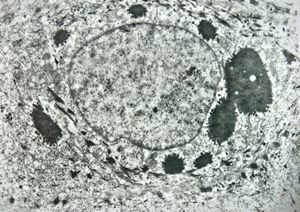

F, 24y. | molluscum contagiosum … virions

F, 24y. | molluscum contagiosum

F, 24y. | molluscum contagiosum